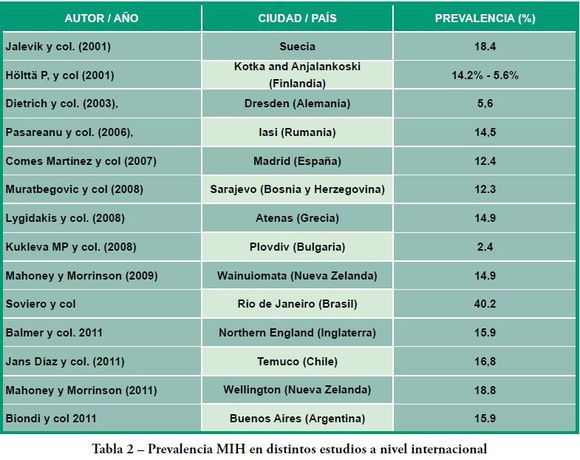

Los valores de prevalencia reportados por diferentes autores son heterogéneos variando entre un 2.4% y un 44% en el mundo (Tabla 2). En una revisión sistemática publicada en 2010(21) sobre prevalencia y diagnóstico de MIH quedan expuestas las diferencias metodológicas entre los estudios presentados por diferentes autores, tales como criterios diagnósticos, estandarización de los evaluadores, condiciones de examen, edades y condiciones sociales de los grupos que integraron las muestras que podría en parte dar respuesta a esta variabilidad.